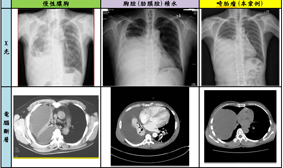

比較圖_慢性膿胸、胸腔(肋膜腔)積水、畸胎瘤

本案例係因腫瘤影像之表現特殊,以純水囊狀來呈現,即使經多年來數次就醫,仍長久以來被認為是慢性膿胸、肋膜積水等等病因來治療,以致無法獲得正確之治療。縱膈腔腫瘤的治療以外科手術為主,傳統開胸手術包含正中胸骨切開或側後胸切開術,但近年來因微創胸腔鏡手術發展,我們僅用一個4公分之側胸切口及一個1公分的引流管傷口,便將其巨大囊腫取出,病患術後恢復良好迅速,且將來無復發之可能。

畸胎瘤發生年齡可從2歲至70幾歲,男女發生率無明顯差異。腫瘤本身由2個或3個胚胎發育層的幾種不同類型的組織構成,這些組織可由成熟的、非成熟的或混合型成分所組成。常發生於卵巢,睪丸等生殖器官。但也可發生於後腹腔或縱膈腔,而以縱膈腔腫瘤而言,畸胎瘤大約佔了一至兩成左右,其實並不常見,畸胎瘤腫瘤本身可為良性或惡性,在縱膈腔內大部分為良性腫瘤,且腫瘤大部分含有較多實質的部分,大部分可由電腦斷層來診斷,但像本案例許女士這樣純囊狀且巨大之畸胎瘤較為罕見,醫學文獻中僅有零星案例報告,因此容易被誤判。